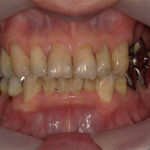

当院で行った歯周病治療の症例